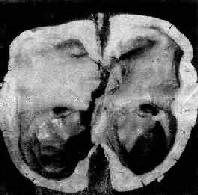

轻度脑积水时,脑室轻度扩张,脑组织呈轻度萎缩。严重脑积水时,脑室高度扩张,脑组织受压萎缩、变薄,脑实质甚至可菲薄如纸,神经组织大部分萎缩而消失(图16-9)。

图16-9 脑积水

侧脑室高度扩张,脑组织受压萎缩变薄